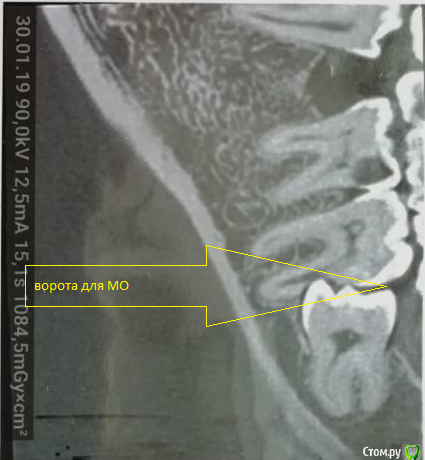

___49___ Опубликовано 30 января, 2019 Поделиться Опубликовано 30 января, 2019 (изменено) Дано на Rg: Вижу два варианта решения задачи. - могу убрать 8ку с одномоментной гемисекцией ( заранее пролеченного 7го зуба) дистального корня 7ки . Далее вкв в мезиальный корень 7ки , лечение 6ки под коронку и изготовление мостовидного протеза с опрой на 6\7 и консолью 5ка . - можно депульпировать 7ку , во время удаления 8 ки закрыть перфу прорутом . 2 вариант на мой взгляд менее прогнозируемый .... у кого какие мысли коллеги ? Изменено 30 января, 2019 пользователем ___49___ Ссылка на комментарий

___49___ Опубликовано 30 января, 2019 Автор Поделиться Опубликовано 30 января, 2019 (изменено) При предложенном Вами выше варианте дальнейшего протезирования - не факт.почему ? 6ка после пульпита будет , пломба на 1\3 или 1\2 зуба выйдет(пардон вам этого не видно наверное, виноват, добавлю срезы ) , коронки пилить будет кадкам , консоль в перед при опоре на 1.5 зуба вполне жизнеспособная конструкция , затруднения в гигиене - суперфлос в руки ( гигиена это общая проблема - либо есть либо нет) Изменено 30 января, 2019 пользователем ___49___ Ссылка на комментарий

___49___ Опубликовано 31 января, 2019 Автор Поделиться Опубликовано 31 января, 2019 (изменено) Процесс ведь там не кариозный,а вполне себе асептический,почему бы не убрать 8ку,заполнить лунку графтом,ушить герметично и понаблюдать?На счет асептического сомнения есть , попробую нарисовать .А 7 живой? Как пульпа реагирует?Если живой - убрать 8, дать зажить ране 3-4 недели, переоценить 7. Он вполне может остаться живым.7ка живая - на холодное реакция выраженная, но не продолжительная , перкуссия болезнена ( но это не из-за Pt а из-за соприкосновения с 8 кой) Ваше предложение интересное, как и выше предложенные варианты , спасибо всем за участие . Буду говорить с пациентом , о этапах и рисках всех вариантов . Изменено 31 января, 2019 пользователем ___49___ Ссылка на комментарий